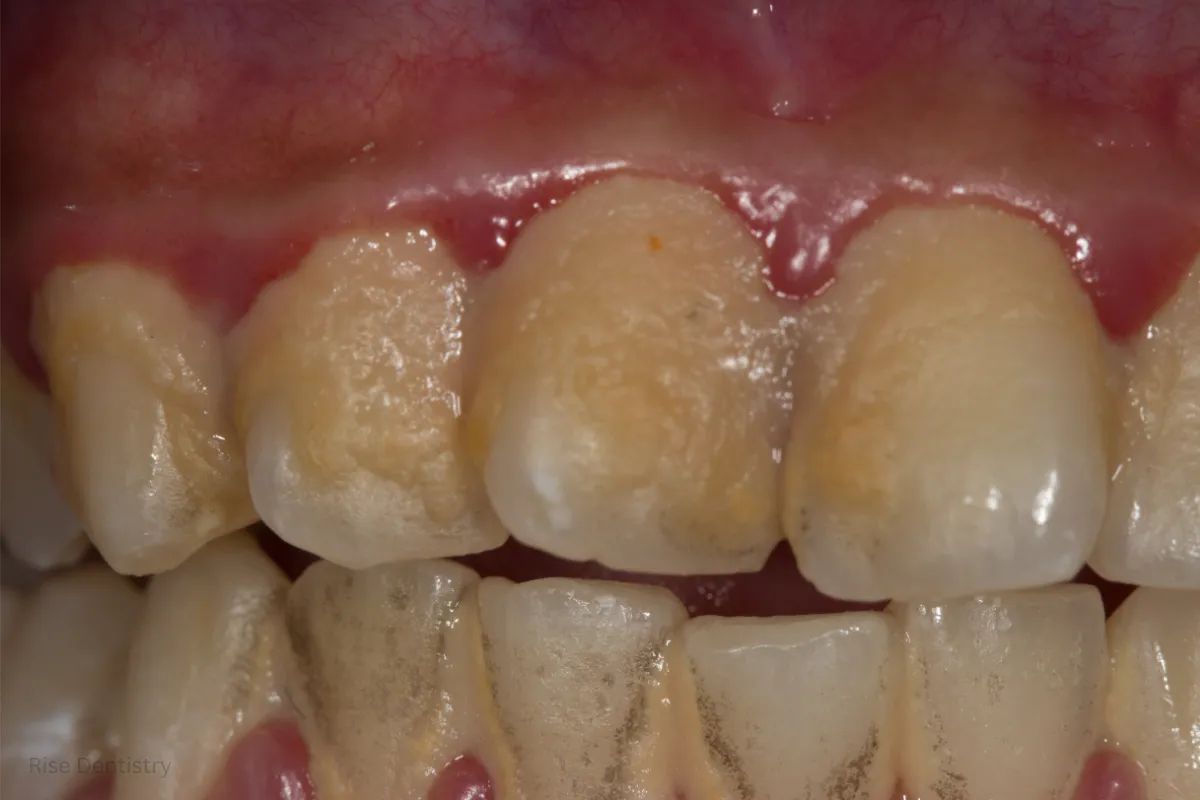

Before Treatment

Before care, gums often show gum inflammation, swelling, and bleeding while brushing. Persistent bad breath or a sour taste can signal infection and bacteria buildup under the gums.